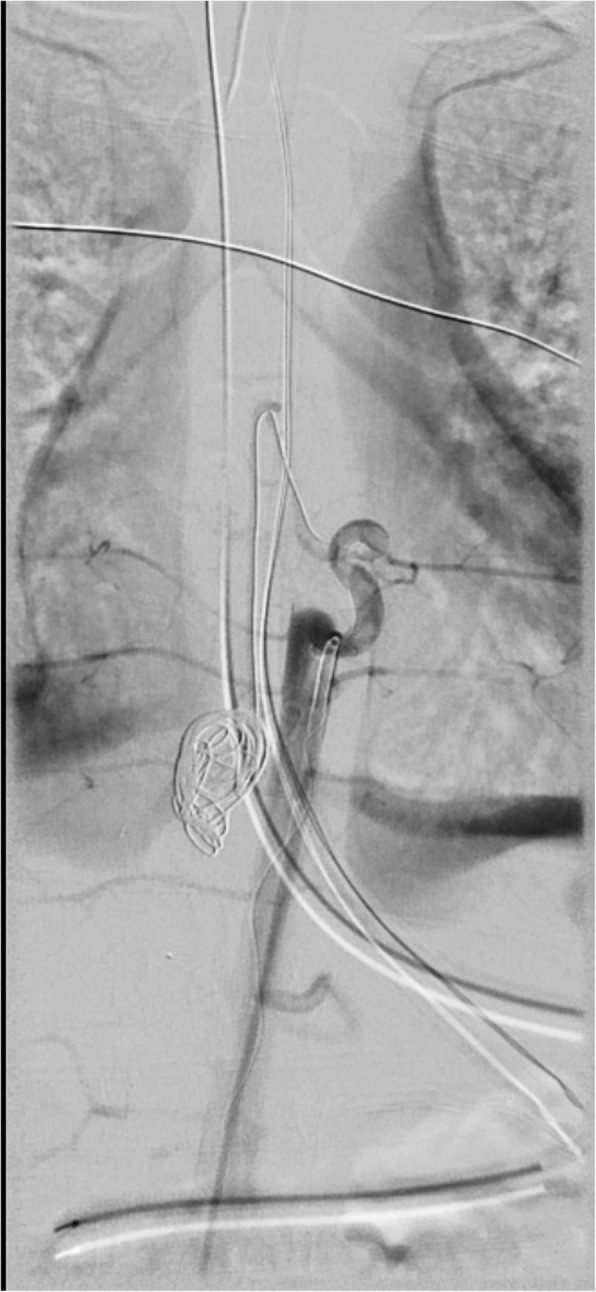

Osteoplastic laminotomies from T6-T12 were performed. The dura was opened and the intradural, intramesenchymal hematoma was evacuated. There were two episodes of brisk arterial bleeding with hypotension during resection of the hematoma. She was transfused with 500 cc of packed cells, 100 cc of fresh frozen plasma, 120 ml of albumin, and 750 ml of crystalloids. Total estimated blood loss was 600 ml. Patient required boluses of epinephrine during episodes of bleeding. Infusions of pressor medications was not needed intraoperatively. Hemoglobin was maintained at or above 10 g/dl. Hemostasis was obtained with aneurysm clip placement after bipolar coagulation, cottonoid application, and gentle pressure. Once hemostasis was achieved, the surgery was stopped because the arterial supply from the ventral side of the aneurysm could not be surgically secured. The dura was left open secondary to spinal cord swelling and prominent aneurysm clips were added. The spinal cord was covered with an artificial dural substitute. The fascia and skin of the thoracolumbar spine were closed. Postoperatively, the patient was administered antibiotics and steroids. She was kept sedated and ventilated until the osteoplastic laminotomies were replaced and the dorsal elements of the spine were reconstructed. The patient was taken to the angiography suite from the OR to coil the large aneurysm (Fig. 4). A week later, the child was brought back to the OR for removal of aneurysm clips and reconstruction of posterior elements of the lamina. Intraoperative SSEPs and MEPs remained undetectable in lower extremities.

Fig. 4.

Digital subtraction angiogram of the origin of the anterior spinal artery at T8 on the left. The hairpin turns and the AVM pseudoaneurysm have been embolized with a detachable coil. There is no opacification of the spinal artery except for its origin. The pseudoaneurysm is occluded. Reflux into the intercostal arteries is demonstrated